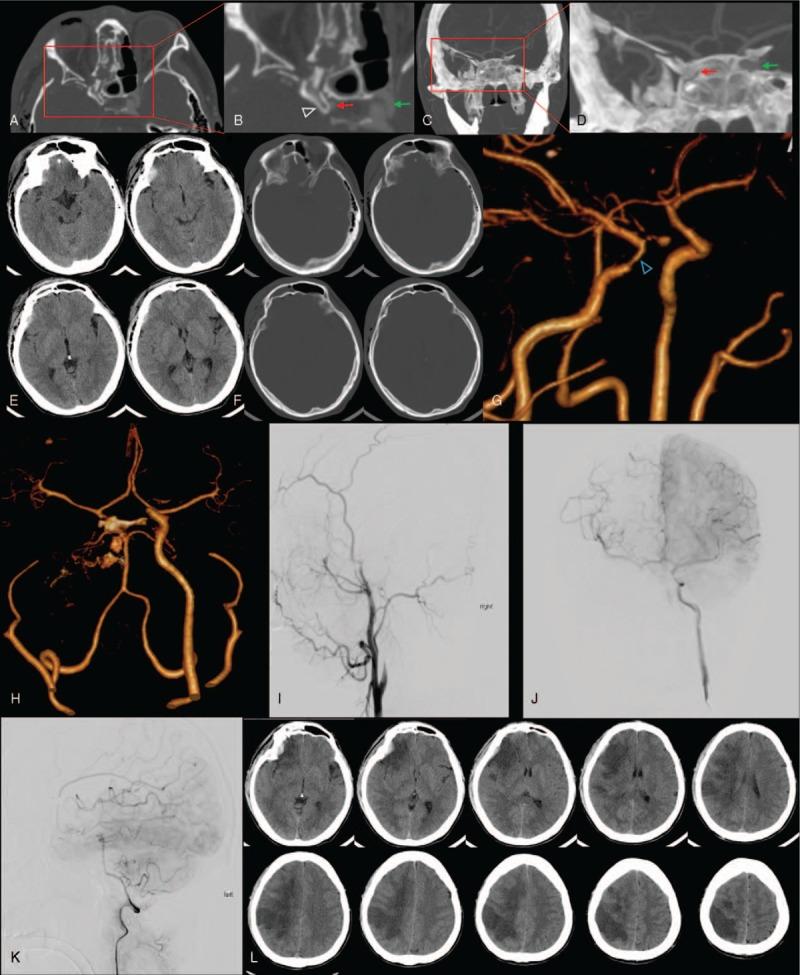

Here we report on 3 BICI cases that demonstrated optic nerve injuries after craniofacial injuries. All 3 patients showed post-trauma vision loss on the injured side.

Optical canal fractures can be found in these patients, and carotid sulcus was compressed by the fragments. Computed tomography angiography (CTA) and digital subtraction angiography (DSA) were performed in all 3 patients.

Case 1 was given no further treatment, except for symptomatic support and rehabilitation therapy. Case 2 was treated with antiplatelet therapy for 3 days, and then a stent was inserted in the injured internal carotid. Case 3 received antiplatelet therapy and a internal carotid compression test was performed simultaneously for 2 weeks, then the injured internal carotid was completely blocked.

Case 1 developed cerebral infarction that resulted in unilateral hemiplegia. Due to timely treatment, the remaining 2 patients had a better prognosis.

这些患者可见视神经管骨折,骨折碎片压迫颈动脉沟。所有3例患者均进行了计算机断层扫描血管造影(CTA)和数字减影血管造影(DSA)。

病例1除给予对症支持和康复治疗外,未进行进一步治疗。病例2接受了3天的抗血小板治疗,然后在受伤的颈内动脉置入支架。病例3接受抗血小板治疗并同时进行颈内动脉压迫试验2周,然后完全闭塞受伤的颈内动脉。

病例1发生脑梗死,导致单侧偏瘫。由于治疗及时,其余2例患者预后较好。